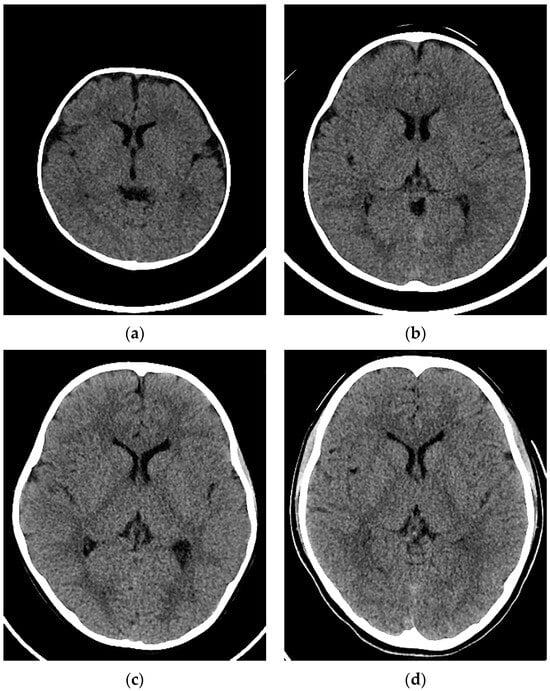

Examples of CT images at 0, 1, 5, and 10 years are presented in Figure 2. The median DLP at each age in integer years was lowest at 0 years and increased with age (Figure 3). The annual increase was relatively large between 0 and 1 years. In contrast, the median ED estimated by the curve method was highest at 0 years and decreased with age (Figure 4). The annual decrease was relatively large between 0 and 1 years and between 1 and 2 years. After that, the median ED decreased slowly and remained almost constant after 9 years. The median ED estimated by the linear method also decreased consistently with age. However, the ED–age profile appeared mildly deformed, creating a shoulder, at 2 and 3 years. The relationship between age and ED was complicated for the simple method. The median ED was high at 0, 1, and 2 years and decreased suddenly at 3 years. After that, it increased slowly up to 7 years, and then it decreased again at 8 years, followed by a slow increase. The median ED obtained by the Radimetrics method tended to decrease with age, but there were obvious up-and-down changes.

Figure 2.

Examples of CT images in a (a) 3-month-old girl, (b) 1-year-old boy, (c) 5-year-old girl, and (d) 10-year-old girl.